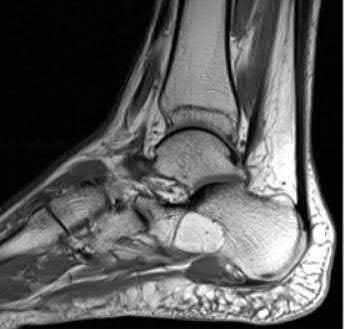

A 25-year-old male sustains an ankle fracture dislocation and undergoes open reduction and internal fixation. He returns to clinic five months following surgery complaining of continued ankle pain and instability with weight bearing. His immediate post-operative AP radiograph is seen in Figure A. Which of the following could have prevented this patient from developing persistent pain?

1) Deep deltoid ligament repair

2) Quadricortical syndesmotic screw fixation

The patient presents with continued ankle pain and instability following open reduction and internal fixation. The radiograph in figure A demonstrates inadequate restoration of fibular length, likely leading to continued tibiotalar instability.

Illustration A demonstrates fibular malreduction with dislocation of the fibula anterior to the tibial incisura. Illustration B shows a comminuted fibula fracture along with a measurement of length from an intact fibula. The arc from the lateral process of the talus to the peroneal groove of the distal fibula is known as the "dime" sign and should remain unbroken if fibular length has been restored. Illustration C demonstrates the use of a push-pull screw and lamina spreader to regain length intraoperatively for a comminuted fibula fracture.

Chu and Weiner review management of malunions of the distal fibula. The authors state that restoration of fibular length, alignment and rotation leads to reduction of the talus, provides a buttress to talar motion in the setting of an incompetent deltoid, and allows the syndesmotic ligaments to heal at the appropriate tension.